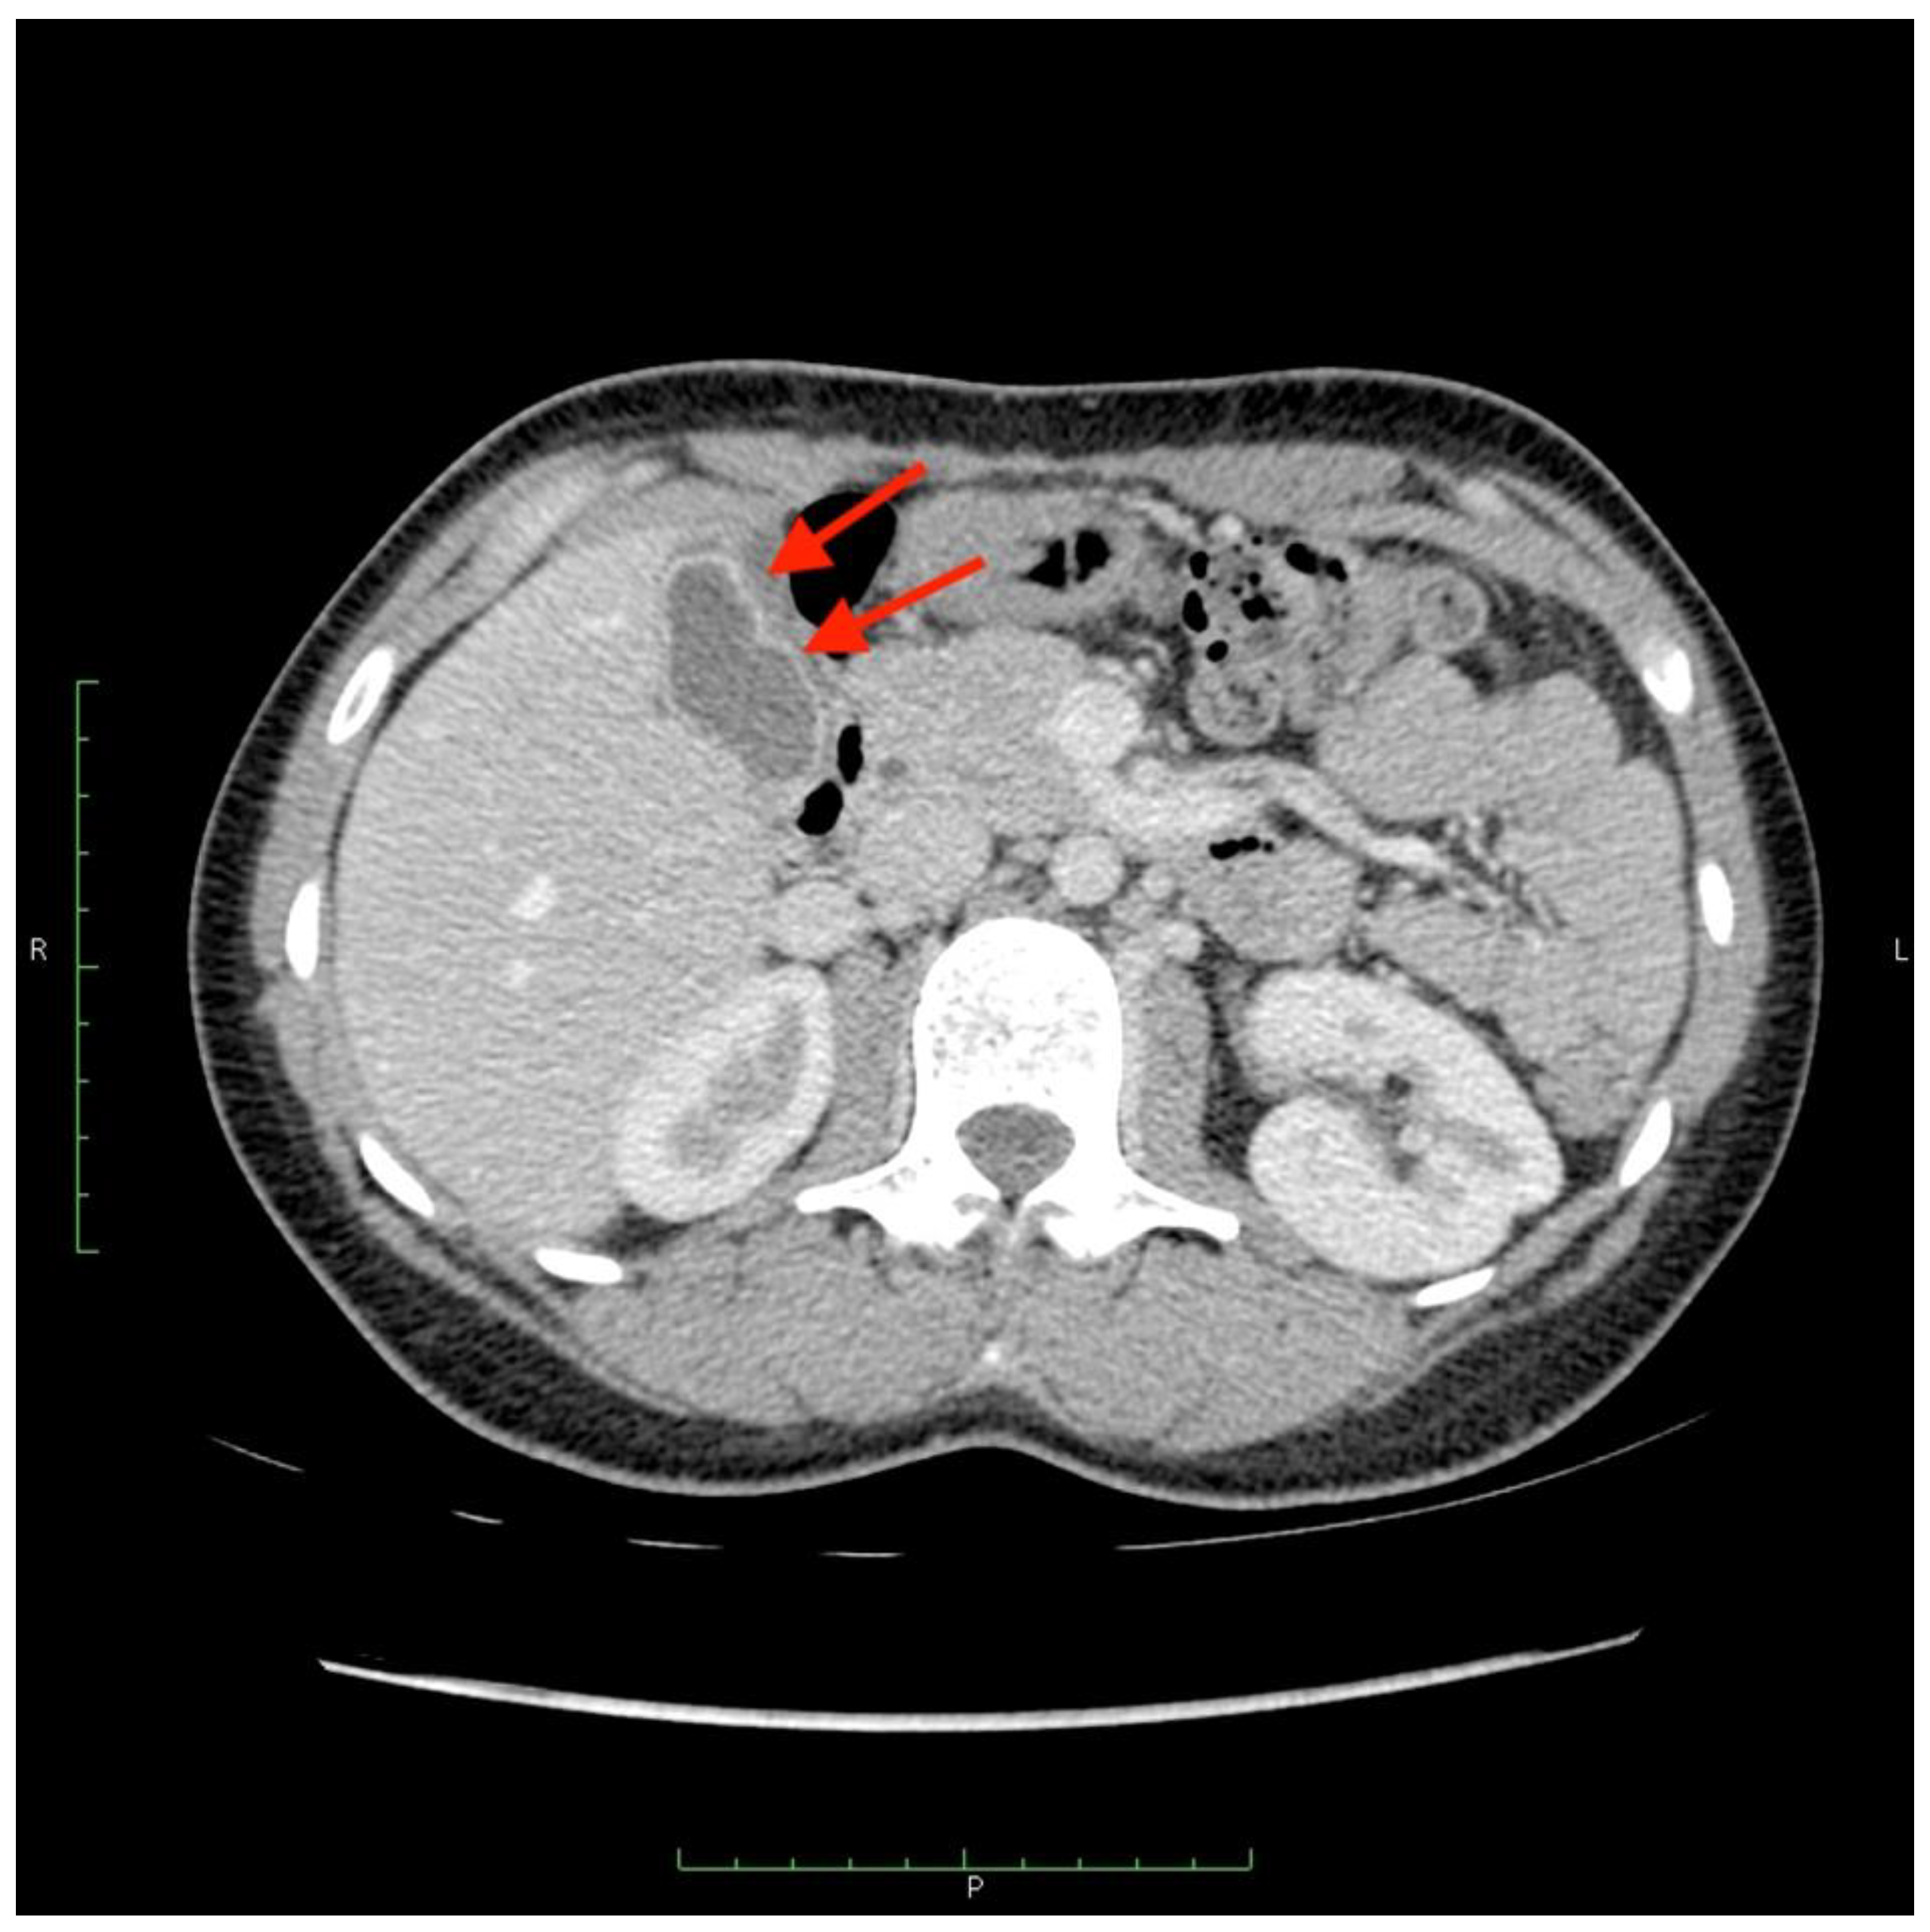

Figure 6.

(A) Angiogram of the left hepatic artery showing falciform artery travelling medially beyond the margin of the liver. (B) Its presence was confirmed on Dyna-CT and showed contrast enhancement of the abdominal wall (arrows) (C), and on SPECT/CT after 99mTc-MAA injection (D) (crosshairs).